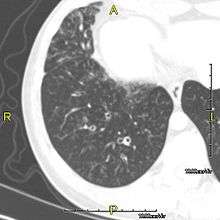

When accompanied by the combination of situs inversus (reversal of the internal organs), chronic sinusitis, and bronchiectasis, it is known as Kartagener syndrome (only 50% of primary ciliary dyskinesia cases include situs inversus).

The main consequence of impaired ciliary function is reduced or absent mucus clearance from the lungs, and susceptibility to chronic recurrent respiratory infections, including sinusitis, bronchitis, pneumonia, and otitis media. Progressive damage to the respiratory system is common, including progressive bronchiectasis beginning in early childhood, and sinus disease (sometimes becoming severe in adults). However, diagnosis is often missed early in life despite the characteristic signs and symptoms.[1] In males, immotility of sperm can lead to infertility, although conception remains possible through the use of in vitro fertilization and, as well as this, there have been reported cases where sperm were able to move.[2] Trials have also shown that there is a marked reduction in fertility in female sufferers of Kartagener's Syndrome due to dysfunction of the oviductal cilia.[3]

Many affected individuals experience hearing loss and show symptoms of glue ear which demonstrate variable responsiveness to the insertion of myringotomy tubes or grommets. Some patients have a poor sense of smell, which is believed to accompany high mucus production in the sinuses (although others report normal - or even acute - sensitivity to smell and taste). Clinical progression of the disease is variable with lung transplantation required in severe cases. Susceptibility to infections can be drastically reduced by an early diagnosis. Treatment with various chest physiotherapy techniques has been observed to reduce the incidence of lung infection and to slow the progression of bronchiectasis dramatically. Aggressive treatment of sinus disease beginning at an early age is believed to slow long-term sinus damage (although this has not yet been adequately documented). Aggressive measures to enhance clearance of mucus, prevent respiratory infections, and treat bacterial superinfections have been observed to slow lung-disease progression. Although the true incidence of the disease is unknown, it is estimated to be 1 in 32,000,[4] although the actual incidence may be as high as 1 in 15,000.